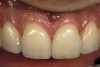

Figure 4  View of the completed central and lateral incisor with margins placed subgingivally, but maintaining tissue health.

Figure 4

The most common reasons to extend a margin below tissue are: caries below gingiva; old restorations that already exist below gingiva; to achieve adequate tooth preparation length for proper retention and resistance; to make significant contour alterations; to hide the margin when the tooth is discolored (Figure 3 and Figure 4); and to hide the margin when the restorative material of choice demonstrates optical properties different from those of the natural tooth such that the margin would be highly visible. Regardless of why a subgingival margin is chosen, there are 2 negative responses that may occur.